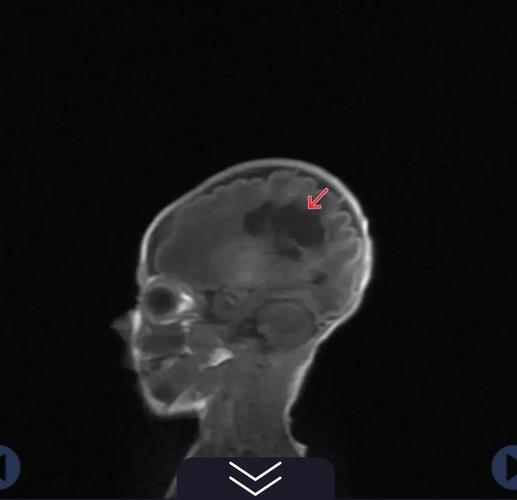

影像学上的表现

- CT扫描:

- 急性期:低密度灶。

- 慢性期(形成软化灶后):边界清晰的低密度灶,其密度与脑脊液相近,由于体积缩小,局部可能会有脑沟、脑池增宽或脑室局部扩大的现象(即脑萎缩)。

- 磁共振扫描:

- T1加权像(T1WI):呈低信号(很黑)。

- T2加权像(T2WI):呈高信号(很白)。

- 液体衰减反转恢复序列(FLAIR):呈高信号,能更好地显示与脑脊液区分开来的病灶。

- 特征性表现:软化灶的信号特点与脑脊液几乎完全一样。